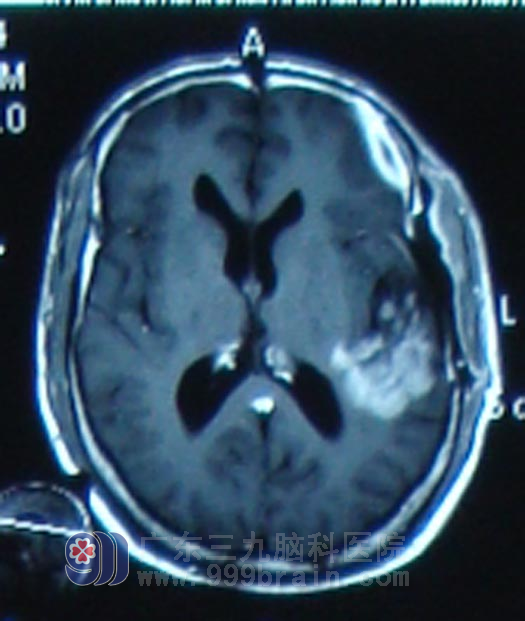

患者朱先生, 35岁,2011年10月21日无诱因出现头痛不适,且程度剧烈,伴言语不清,但是未予重视4天之后头痛正传未见缓解,还出现了呕吐数次,出现“癫痫”症状,表现为四肢抽搐,头后仰,双眼紧闭,持续2-3秒之后自行缓解,当地医院头颅CT及MR显示左颞叶占位,10月28日即来广东三九脑科医院就诊,来院时,朱先生神志清楚,不完全性失语,右侧肢体肌力稍减弱。完善相关检查且排除手术禁忌症后,11月4日行手术治疗,手术部分切除,术后病理为弥漫性大B细胞淋巴瘤,术后症状好转后转入肿瘤综合治疗中心行大剂量甲氨蝶呤化疗,化疗一程后复查MR显示原强化范围及水肿范围较前明显缩小。朱先生恢复到以往的工作和生活,医嘱定期复查。

治疗后